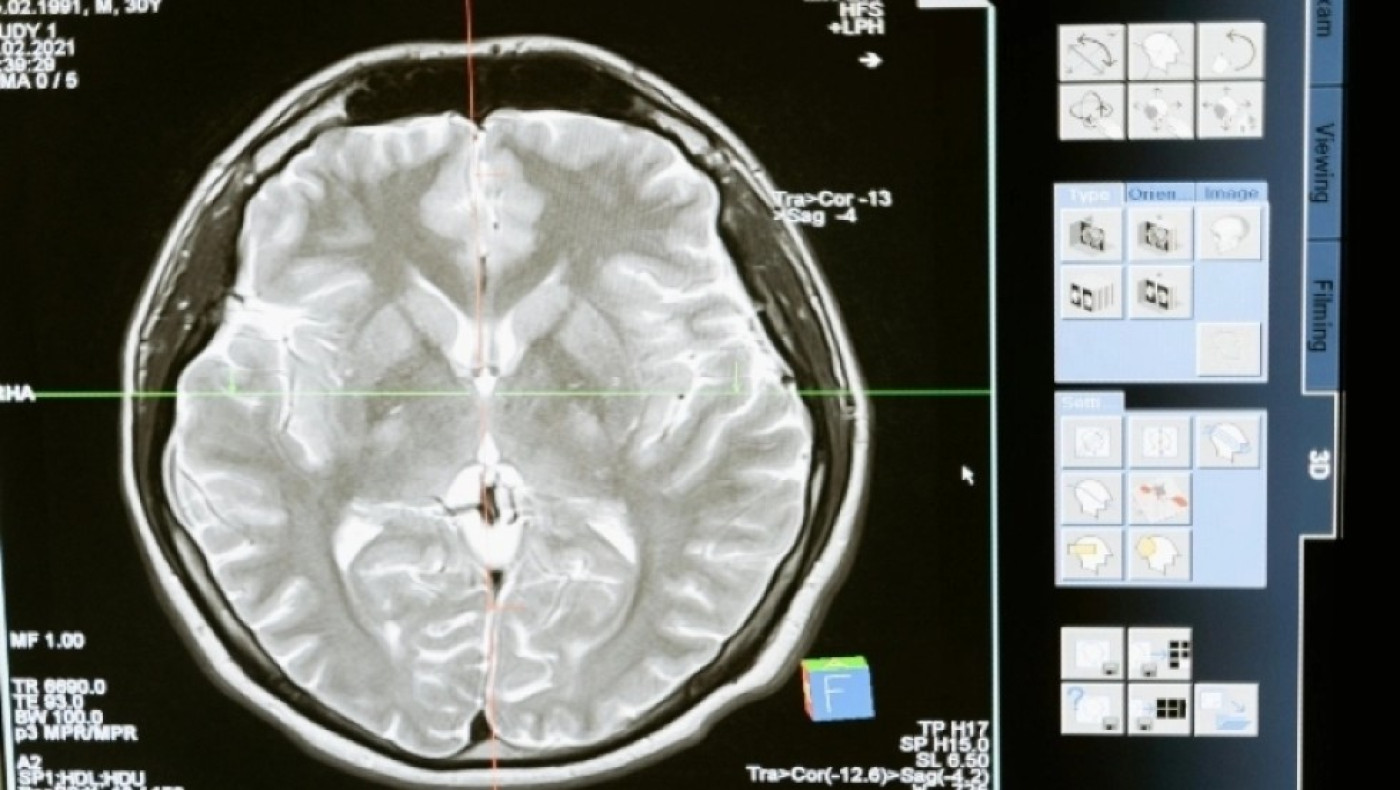

Σε μια εποχή όπου η ανησυχία για τη μείωση της ανθρώπινης νοημοσύνης έρχεται κατά καιρούς στην επιφάνεια, ένα συναρπαστικό σύνολο στοιχείων παρουσιάζει μια αντίθετη αφήγηση: οι εγκέφαλοι μας μεγαλώνουν. Μια πρόσφατη μελέτη που διεξήχθη από το UC Davis Health έφερε στο φως ότι, σε σύγκριση με τα άτομα που γεννήθηκαν τη δεκαετία του 1930, όσοι γεννήθηκαν τη δεκαετία του 1970 διαθέτουν εγκεφάλους με αυξημένο όγκο και επιφάνεια, όπως αναφέρει το Newswise.

Η έρευνα αυτή αποτελεί μέρος της συνεχιζόμενης μελέτης Framingham Heart Study (FHS), η οποία ξεκίνησε πριν από 75 χρόνια και παρακολουθεί σχολαστικά τους δείκτες υγείας χιλιάδων συμμετεχόντων, συμπεριλαμβανομένων των διαδοχικών γενεών. Η μελέτη, που εξέτασε τα μεγέθη του εγκεφάλου 3.226 ατόμων από το 1999 έως το 2019, διαπίστωσε αύξηση του όγκου του εγκεφάλου κατά 6,6% και της επιφάνειας του εγκεφάλου κατά 15% μεταξύ όσων γεννήθηκαν την τελευταία δεκαετία.

Η πιθανή σχέση μεταξύ μεγαλύτερου μεγέθους εγκεφάλου και άνοιας είναι ιδιαίτερα ενδιαφέρουσα. Ο Charles DeCarli, επικεφαλής συγγραφέας της μελέτης, προτείνει ότι: «Οι μεγαλύτερες εγκεφαλικές δομές μπορεί να αντανακλούν τη βελτιωμένη ανάπτυξη και υγεία του εγκεφάλου, αντιπροσωπεύοντας ένα μεγαλύτερο απόθεμα εγκεφάλου». Αυτό θα μπορούσε να λειτουργήσει ως ρυθμιστικό παράγοντα έναντι των εξουθενωτικών επιπτώσεων των ασθενειών του εγκεφάλου που σχετίζονται με την ηλικία, όπως η νόσος Αλτσχάιμερ και οι συναφείς άνοιες, αργότερα στη ζωή.